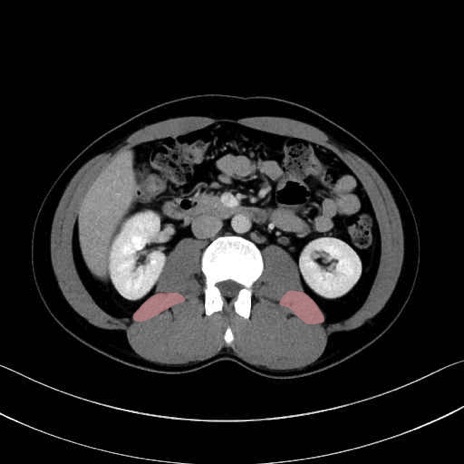

腰方形筋(quadratus lumborum muscle)のCT画像の解剖

大腰筋 (Psoas major)

腸骨筋 (Iliacus)